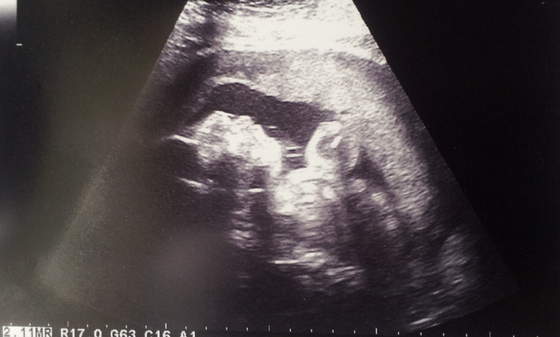

Zdjęcia mam ale takie jakieś mało wyraźne

A to Filip z mamusinym noskiem, biedactwo ladniutkie po mamusi ale brzydki profil tez po mamusi, nie bedziemy mu robic zdjec profilu :PPP